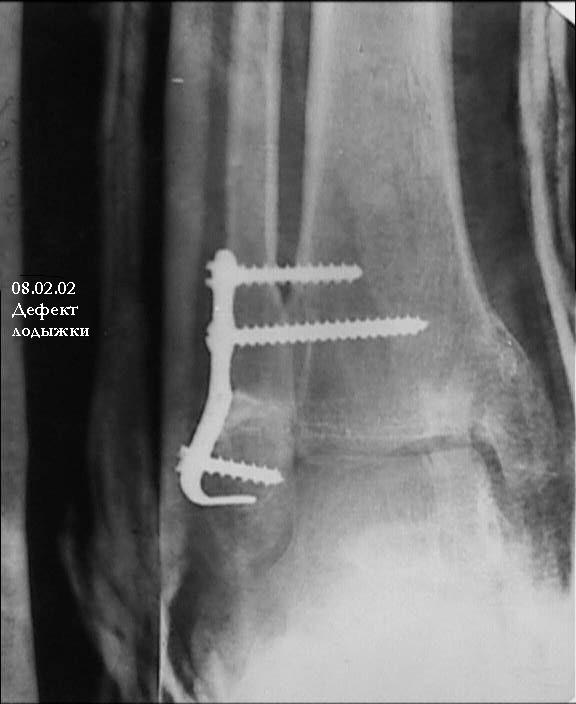

Провели костную аутопластику дефекта, металлоостеосинтез наружной лодыжки Г-образной пластиной и 4 винтами. Снимок 1, Снимок 2.

При проведении винтов выше перелома выявлен остеопороз. Есть опасность, что винты не удержат пластину при ранних нагрузках, поэтому провели винты через межберцовый синдесмоз.